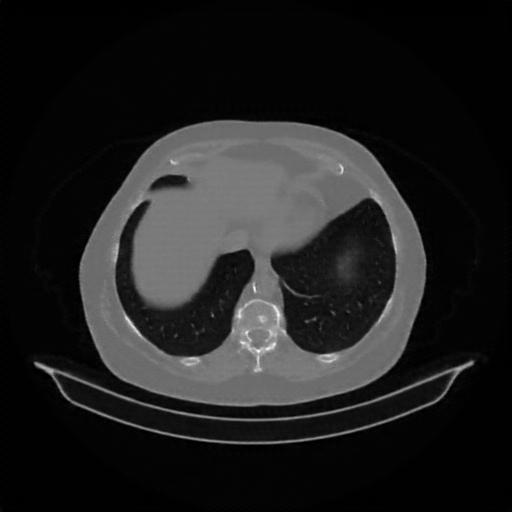

Reconstructed NATIVE CT scan (cycle consistency)

Full window (WL 1023.5, WW 4095 β†’ Low βˆ’1024, High +3071)

Lung window (WL -600, WW 1500 β†’ Low βˆ’1350, High +150)

Mediastinum window (WL 40, WW 400 β†’ Low βˆ’160, High +240)